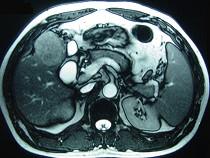

问题 男性,60岁,右上腹胀不适,右肝区叩击痛,影像检查如图,最可能的诊断是()

选项 A.肝硬化 B.肝硬化、外生性肝癌 C.肝硬化、腹腔间质瘤 D.肝硬化、膈下脓肿 E.肝硬化、结节性增生

答案 B